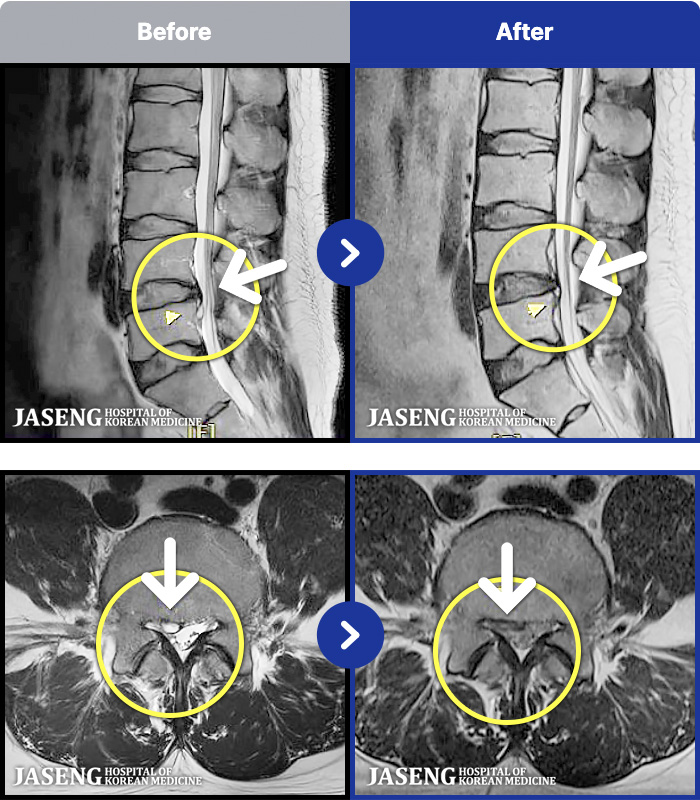

MRI ġ

1,301 MRI ũ ʸ Ȯϼ.